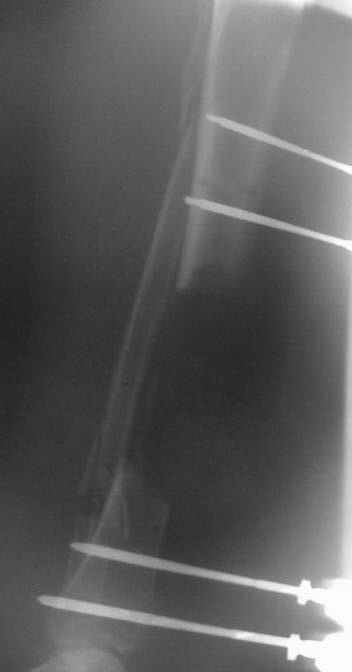

This Patient have to be treated by using Ilizarov bifocal bone transport, aproximatly as showen here.

from case archives - also see Ilizarov split fibula

"fibula pro tibia" transfer for segmental tibia defects